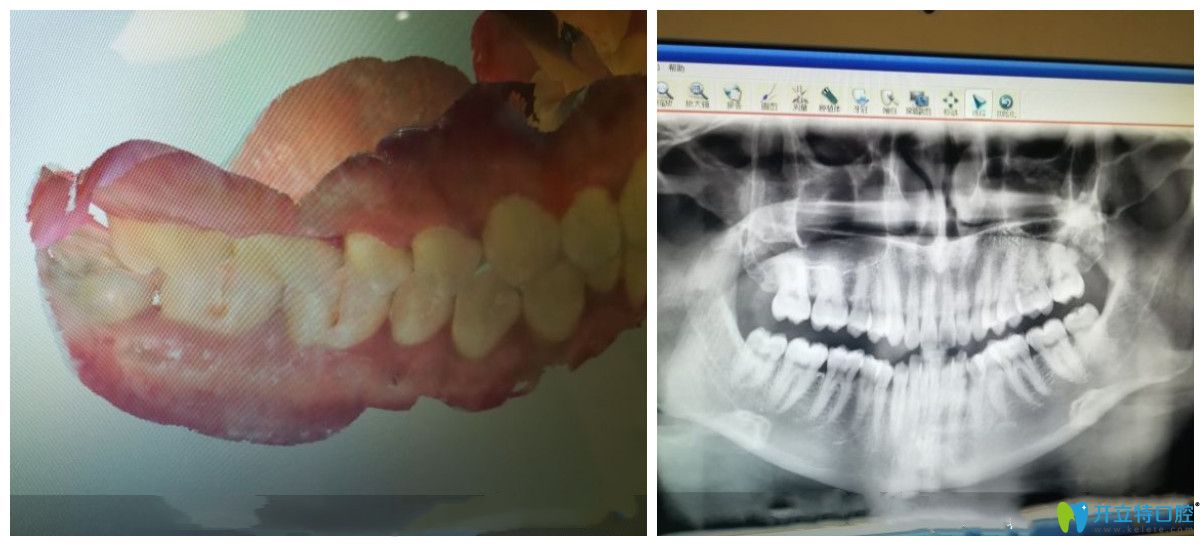

術(shù)前問題:門牙前突,牙齒擁擠不齊

在成都圣貝口腔做隱形矯正前檢查圖